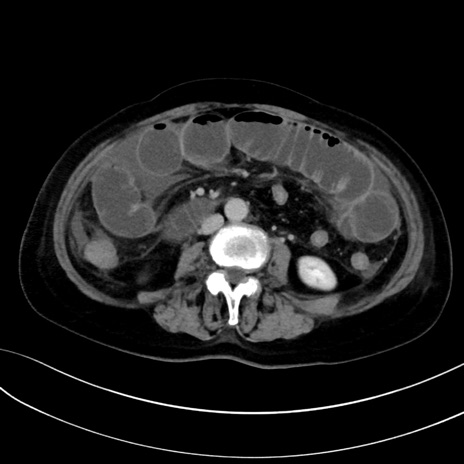

症例13 CT(横断像)1日半後